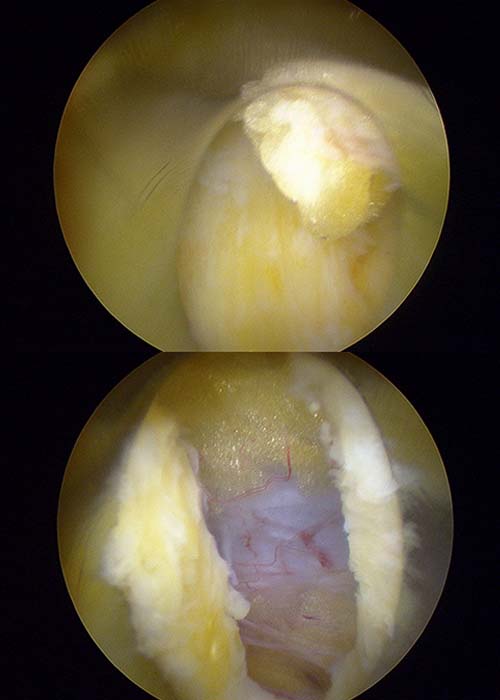

Caso-clinico-Hermia-discal-L5S1

Operamos al paciente mediante una técnica de endoscopia mínimamente invasiva sin producir ningún daño en sus tejidos.

Para este tipo de operaciones, introducimos una aguja que sirve como guía y, dentro de ella, un dilatador que nos permite no perjudicar ni dañar ningún tejido neurológico, muscular u óseo. Posteriormente, accedimos a la zona que queríamos trabajar a través de la cánula. Con un vaporizador especial formado por una punta de láser que trabaja con radiofrecuencia, vamos cauterizando o retrayendo los tejidos. Dicho aparato quirúrgico, nos ayuda identificar de manera óptima y precisa las estructuras que debemos ir limpiando.

Gracias a esta operación, conseguimos eliminar por completo la compresión del nervio, logrando de manera óptima la circulación de la sangre alrededor de la zona mencionada y descomprimiendo de manera completa todas las estructuras neurológicas.